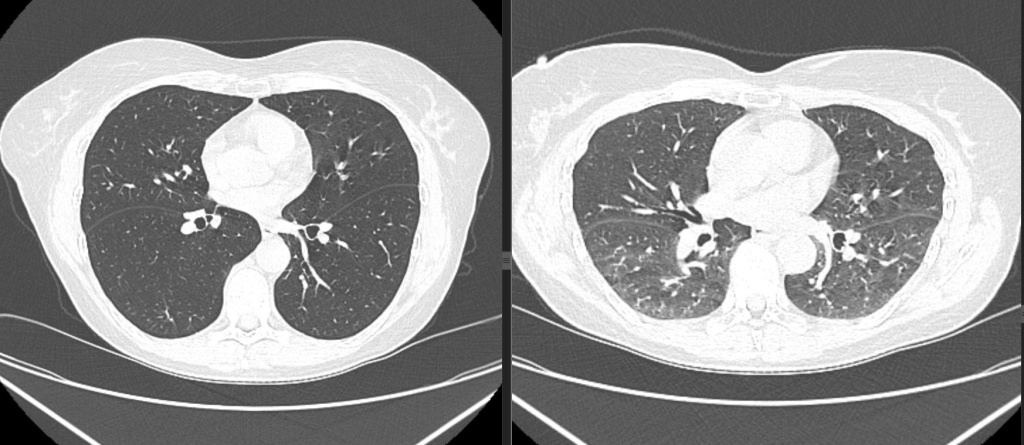

КТ легких (органов грудной клетки)

КТ органов грудной клетки — это современный, доступный и высокоинформативный метод лучевой диагностики. Благодаря послойному сканированию врач получает детальную информацию о состоянии органов грудной клетки, включая мягкие ткани, сосуды и бронхиальное дерево. Этот метод значительно эффективнее рентгенографии, так как позволяет выявлять даже небольшие очаги поражения за счет получения снимков в различных проекциях, исключая наложение костных структур.

КТ легких позволяет выявить патологические изменения воспалительного, инфекционного или опухолевого характера на ранних стадиях. Регулярное проведение исследования с виртуальной бронхоскопией помогает отслеживать динамику очаговых изменений и визуализировать бронхоальвеолярную систему.

Данное исследование позволяет выявить стойкие участки повышения пневматизации легочной ткани - так называемые «воздушные ловушки», кроме того выявляет признаки туберкулеза, хронических и острых воспалительных заболеваний, онкопатологии, лимфопролиферативных заболеваний и аномалий развития, позволяет оценить функцию легочной паренхимы.